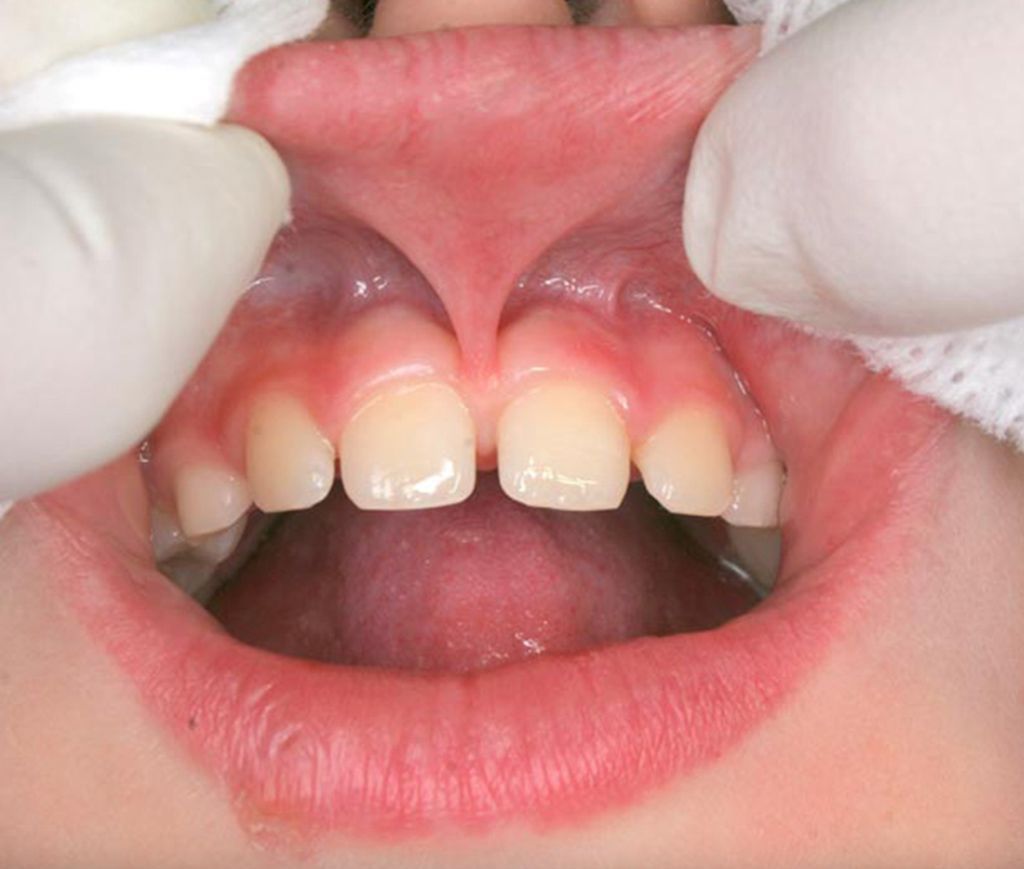

Stramt leppebånd oppstår når bindevevet som fester overleppen eller underleppen til tannkjøttet er for kort eller stramt. Dette kan begrense leppens bevegelighet og skape både funksjonelle og estetiske utfordringer. Tilstanden omtales også som

ankyloglossia labii eller leppebåndsproblemer, og kan ramme både barn og voksne. Merk at vi er en privat tannklinikk og ikke utfører denne behandlingen på barn.

Et stramt leppebånd kan føre til at leppen trekker seg opp når man smiler, at mellomrommet mellom fortennene ikke lukker seg, eller at barn strever med amming. Hos Tannlegene på Sinsen har vi erfaring med å diagnostisere og behandle stramt leppebånd på en trygg og effektiv måte. Sørg for å bestille time hos tannlege Nedd, da han er vår mest erfarne tannlege på dette området og utfører denne behandlingen jevnlig. Merk at vi ikke utfører behandlingen på barn. Behandlingen koster NOK 3990,-.

- Hos barn: Mellomrom mellom fortennene, problemer med uttale og vansker med å bevege leppen normalt.

- Tannstillingsproblemer, ofte med mellomrom mellom fortennene